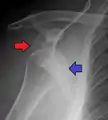

Posterior (backward)

Posterior dislocations are uncommon, and are typically due to the muscle contraction from electric shock or seizure.[6] They may be caused by strength imbalance of the rotator cuff muscles. People with dislocated shoulders typically present holding their arm internally rotated and adducted, and exhibiting flattening of the anterior shoulder with a prominent coracoid process.

Posterior dislocations may go unrecognized, especially in an elderly person[12] and in people who are in the state of unconscious trauma.[13] An average interval of 1 year was noted between injury and diagnosis in a series of 40 people.[14]